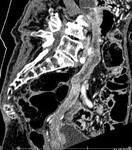

[画像診断]先天性小腸閉鎖について 2010-08-06